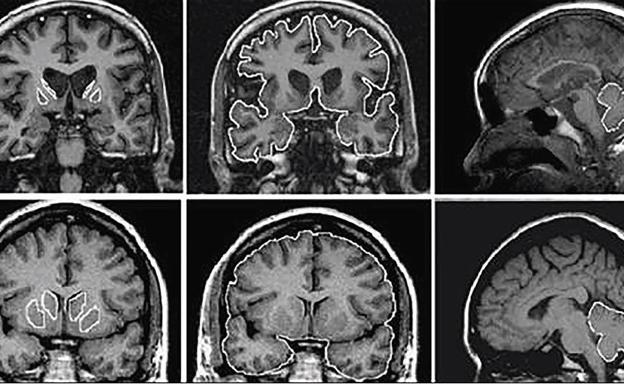

Una serie de variaciones genéticas hereditarias pueden predisponer a las personas a la sinestesia, lo que abre una puerta para comprender mejor trastornos como el autismo